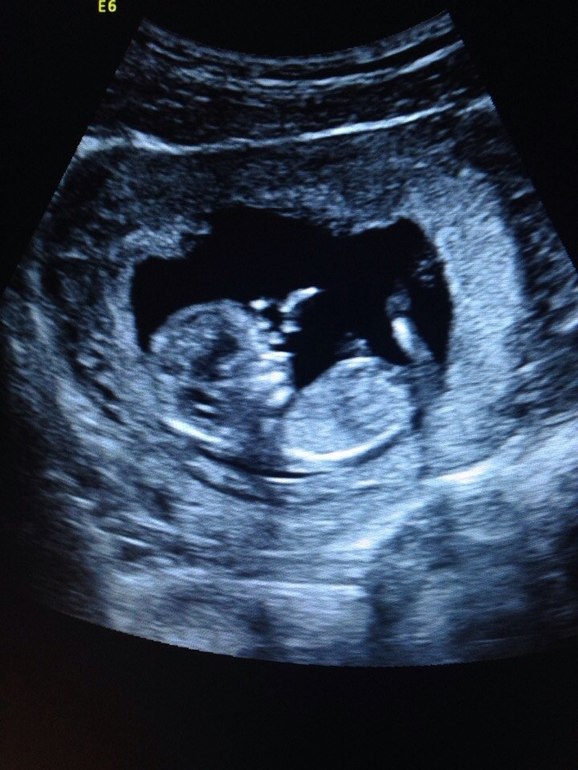

Утром была в ЖК на скрининге, совсем его не боялась..но заранее себя настроила...что могут не показать малыша (многие девочки писали, что им врачи экран не поворачивали).

Врач спокойно все осмотрел, под конец вынес вердикт, что слава Богу все на месте и нормально развивается

В самом начале услышала как бьется сердце - до сих пор не верится, что жизнь развивается внутри меня))))После обследования показали на экране кроху и разрешили сфотографировать))Я долго вглядывалась в лицо и решила, что на папку нашего похож))

Спасибо большое!)))а мне носик видно, губки и глазки)))ну вот мне профиль малыша напомнил профиль мужа)))себя я там пока не увидела)))